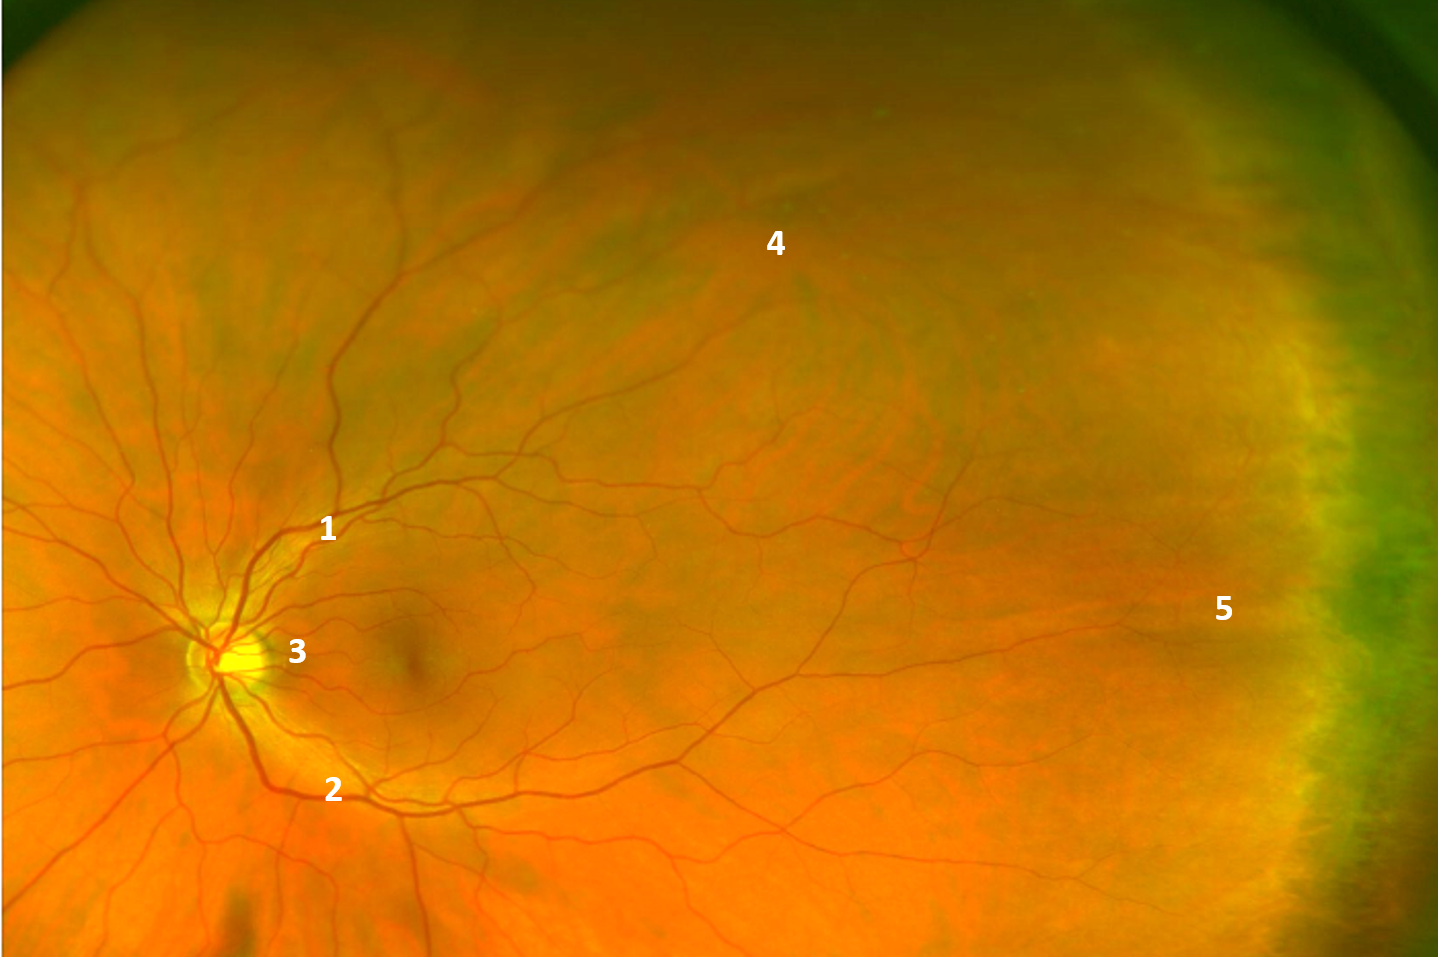

The widefield image shown here illustrates the key vascular features of the retina. The superior vascular arcades (1) and inferior vascular arcades (2) emerge from the optic disc, running temporally in an arcuate shape. These vessels are branches of the central retinal artery which divide further as you move away from the optic nerve.

The cilioretinal artery (3) is visible on this image also.

The vortex vein ampullae (4) are an important anatomical landmark as they define the location of the equator. These may vary in number from 4 to 8 in each eye, however most people will have 4 or 5. A vortex vein ampulla may be described as the convergence of multiple large choroidal vessels into a single large ampullar trunk.

The long posterior ciliary nerve (5), while not vascular in nature, may be seen on peripheral examination and it is helpful to be able to identify this also. Adjacent to the long posterior ciliary nerve is the dark band of the ciliary body. The point at which this joins the retina is termed the ora serrata, and it typically has a serrated appearance.